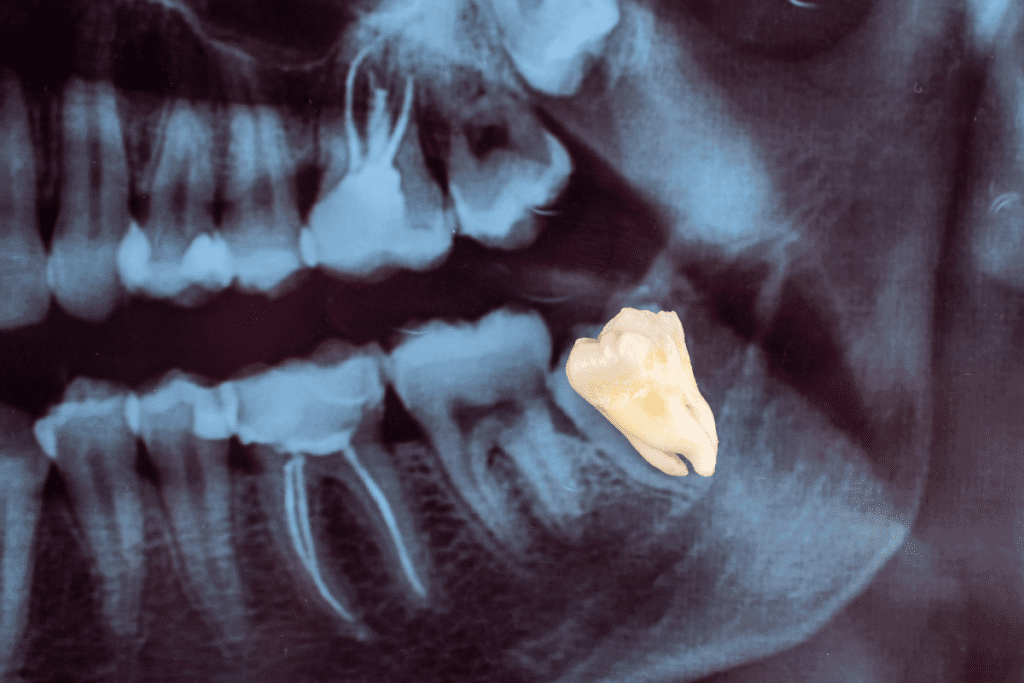

If any of these sound familiar, it’s worth getting an X-ray to understand exactly what’s happening beneath the surface. Here at Pure Dental in Truro, we can assess the position of your wisdom teeth and clearly talk you through your options, helping you understand what (if anything) needs to happen next.

If a clinical assessment is needed, we’ll carry out a thorough examination and, where appropriate, take X-rays to see exactly what your wisdom teeth are doing beneath the surface. From there, we’ll explain your options honestly – whether that’s a period of monitoring, treatment to manage an infection, or a conversation about extraction. Nothing happens without your full understanding and agreement, and we’ll take the time to make sure you feel completely comfortable with whatever comes next.

A wisdom teeth assessment at Pure Dental is straightforward and nothing to worry about. One of our experienced dentists will examine the back of your mouth, discuss your symptoms, and, if needed, take X-rays to see exactly how your wisdom teeth are positioned beneath the gums.